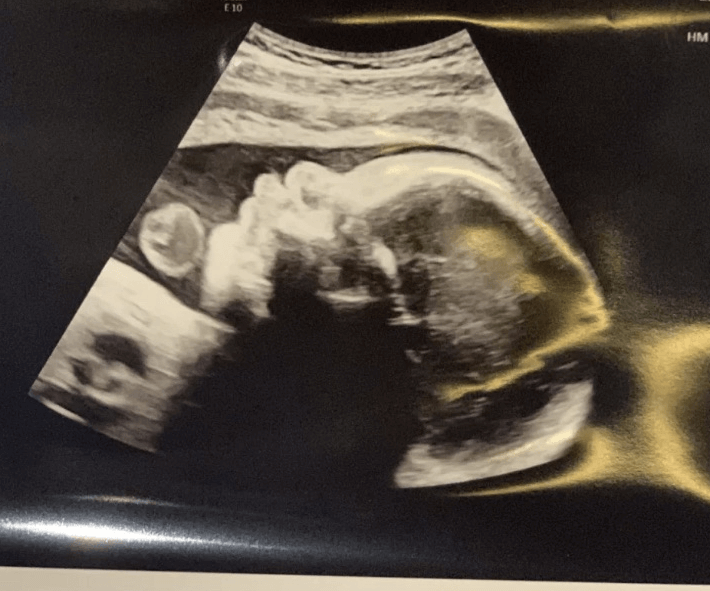

胎停5個月後打絨促再備孕,回過頭來發現原來早有胎夢暗示

胎停又稱胎停育,是指妊娠早期胚胎因某種原因所致發育停止,在臨床上常提示必然流產的結局。對於只是偶爾一次胎停的女性來說,在流產過後,子宮內膜以及卵巢功能已經恢復正常,則可以再備孕要孩子,但是此時間段一般要間隔3~6個月的時間。對於已經出現過兩次或兩次以上胎停的女性,則需要遵醫囑進行相關的檢查,比如內分泌檢查、甲狀腺功能檢查等,瞭解具體原因。下面就來分享一位寶媽胎停育5個月後重新成功懷孕的案例,以給廣...